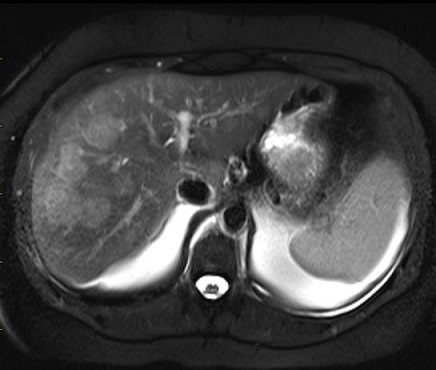

Image IRM

typique de hemangiome : Methode IRM est tres

performance de diagnostique hemagiome du foie : aspect

hyposignale en T1 et hypersignal en T2 . Cinetique de

rehaussement avec de contrast intraveineuse est resemble a

celle du TDM

Image hyposignal d'une

hemangiome du foie en coupe axiale de IRM a

travers du foie ponderee en T1 |

|

Image hypersignal

du mêm cas en coupe axiale de IRM a travers du

foie ponderee en T2 fat-sat |